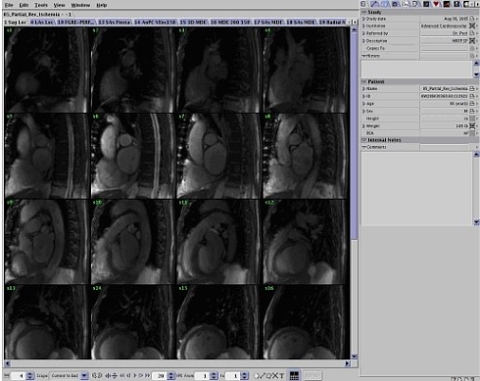

The ReportCARD window opens over the entire screen. The display shows images from series one (1) of the select exam.

Figure 9. ReportCARD Window Images